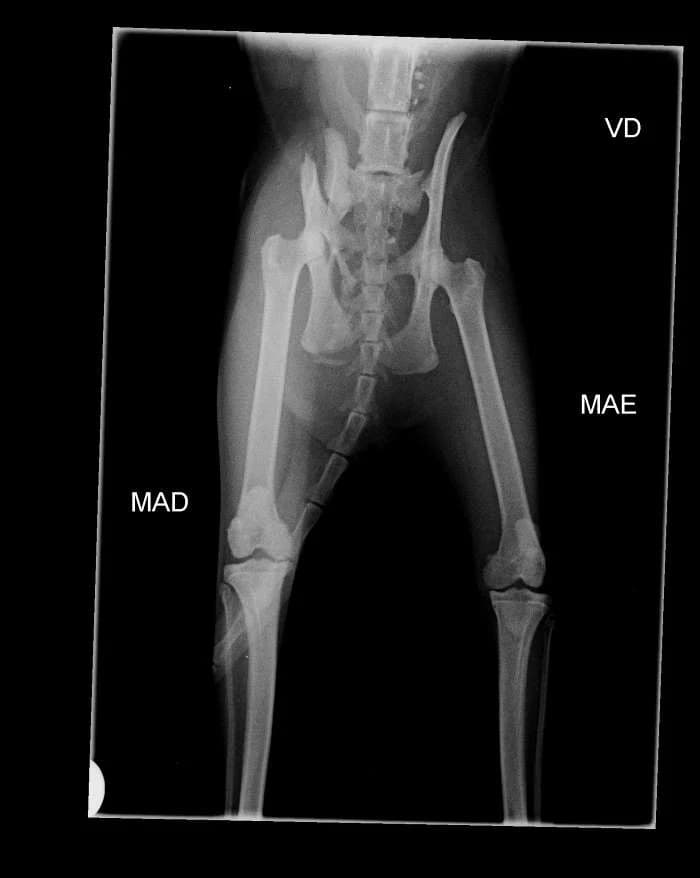

Gena was found run over at Quinta do Conde. There are several fractures in the basin. It needs a lot of rest. We still don't have confirmation that he'll be operated. She's doing antibiotics, anti-inflammatory drugs and painkillers. Gena's a sweetheart! Gena's shy, but she's ready for adoption! Gena is sponsored by António M.